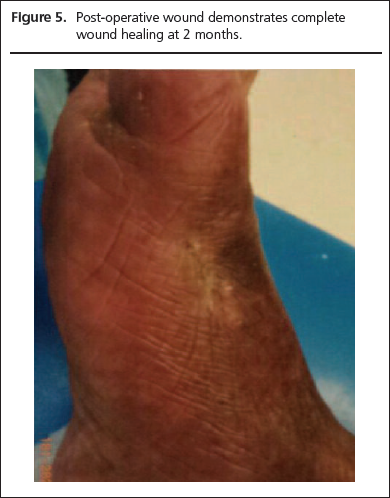

He was treated for acute gout with colchicine. Allopurinol was commenced once the acute inflammation had subsided. Four weeks later, despite near resolution of the ulcerated area, the patient presented again with a painful swollen foot and tiny punched out ulcers on the base of the fore and mid-foot, both interconnected and probing to bone. Radical surgical debridement with complete removal of the tophaceous mass was carried out and 2 months post operatively, there was complete wound healing (Figures 4,5) and the serum urate level had come down to 481 µmol/l.

Figure 4

Figure 5